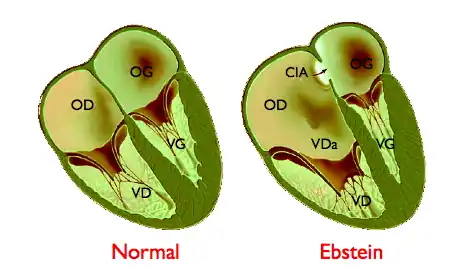

Cette anomalie est responsable d'une modification de l'anatomie fonctionnelle du cœur droit. Normalement, l'atrium (anciennement oreillette) droit (OD) et le ventricule droit (VD) se contractent successivement, la contraction de l'atrium se produisant alors que la valve tricuspide est ouverte, celle du ventricule droit après qu'elle s'est fermée, pour éviter un reflux de sang dans l'atrium. L'implantation trop basse de la valve tricuspide modifie la répartition des cavités. L'atrium droit est dilaté, formé de l'atrium normal et de la partie proximale du ventricule droit (portion « auricularisée » - VDa sur le schéma). Cet atrium a une cinétique anormale, avec une double contraction se produisant aux temps atrial et ventriculaire du cycle cardiaque. Le ventricule droit est quant à lui de dimensions réduites, au prorata de l'importance du déplacement de la valve tricuspide.

- La présence d'une communication inter-atriale (CIA sur le schéma) ou d'un foramen ovale perméable (voir Circulation fœtale), observée dans 50 % des cas au moins, (90 % pour certains auteurs) et qui modifie profondément la symptomatologie en transformant l'anomalie d'Ebstein en cardiopathie cyanogène par passage anormal de sang de l'atrium droit dans l'atrium gauche.